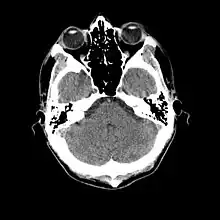

- Cranial computed tomography (CT, invented 1972) proved to be an excellent tool for diagnosing cerebral neoplasms in children, including those found in tuberous sclerosis.[46]

- MR was judged superior to CT imaging for both sensitivity and specificity. In a study of fifteen patients, it identified subependymal nodules projecting into the lateral ventricles in twelve patients, distortion of the normal cortical architecture in ten patients (corresponding to cortical tubers), dilated ventricles in five patients, and distinguished a known astrocytoma from benign subependymal nodules in one patient.[53]

- MR imaging was found to be capable of predicting the clinical severity of the disease (epilepsy and developmental delay). A study of 25 patients found a correlation with the number of cortical tubers identified. In contrast, CT was not a useful predictor, but was superior at identifying calcified lesions.[54]